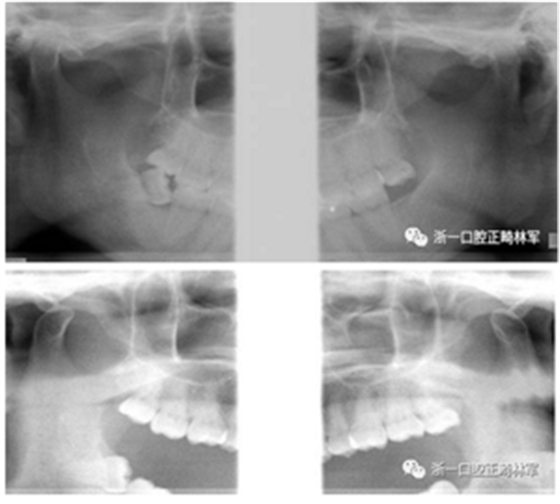

初診張閉口關(guān)節(jié)片:張閉口位關(guān)節(jié)間隙正常。雙側(cè)髁突外形正常,骨皮質(zhì)連續(xù),未見明顯吸收變形。